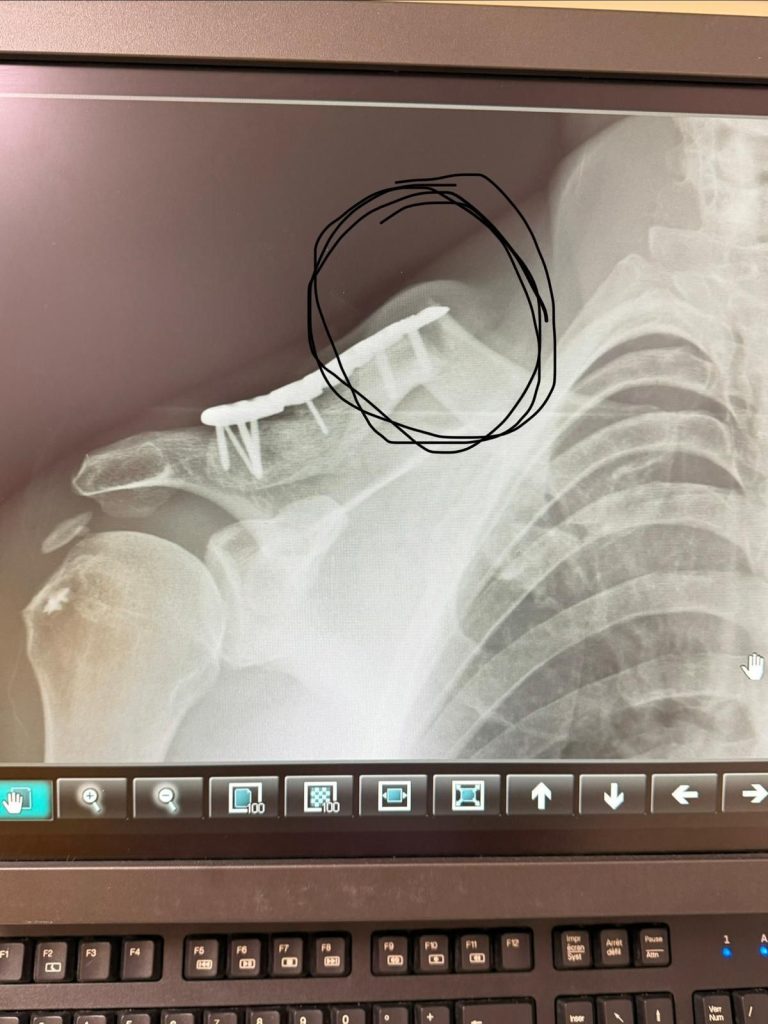

V dôsledku nehody po 140 km si Štefan Svitko poranil pravé rameno a požiadal o repatriáciu do bivaku. Keďže Slovák súťaží v triede Rally GP, toto odstúpenie z etapy znamená, že Dakar sa pre neho skončil. Je to jeho piate predčasné odstúpenie zo 17 účastí a prvé v Saudskej Arábii. Jeho najlepším výkonom bolo druhé miesto v celkovom poradí v roku 2016 a je známy tým, že pravidelne bojuje o čestný titul najlepšieho súkromného jazdca na rally.

“V dôsledku nehody po 140 km si Štefan Svitko poranil pravé rameno a požiadal o repatriáciu do bivaku. Keďže Slovák súťaží v triede Rally GP, toto odstúpenie z etapy znamená, že Dakar sa pre neho skončil. Je to jeho piate predčasné odstúpenie zo 17 účastí a prvé v Saudskej Arábii. Jeho najlepším výkonom bolo druhé miesto v celkovom poradí v roku 2016 a je známy tým, že pravidelne bojuje o čestný titul najlepšieho súkromného jazdca na rally. Prajeme mu skoré uzdravenie.“